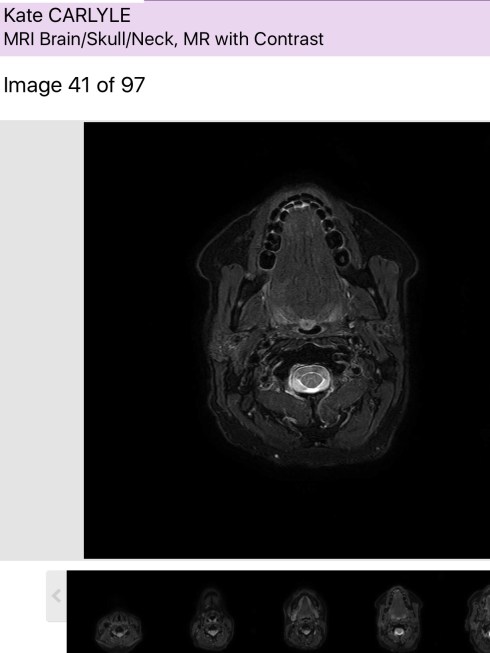

I truly believe that, which is why I’m not completely terrified of a ‘suspicious mass’ recently discovered in my mouth.

It’s coming out in a few days time. The surgeon is highly experienced and during the necessary scans and tests of late has become a good fit in my (now rather extensive) care team.

Whilst acknowledging if this case were for his surgical exam, he would leave things for a few months, he duly pointed out that this is real life and this patient has a nasty cancer history. So, we agreed that after observing for a set period – the ‘watch and wait’ approach is clearly not in my best interests.

This may turn out to be a sublingual gland that is just ‘misbehaving’ given my overall health. Fingers crossed. If it is however, another hit of the ‘Big C’, I’ll deal with it as I have the last three.

Fortunately they won’t have to go through my face (or brain! I was shocked when he mentioned casually that sometimes that is the best/only way to get to the area), they’ll go into the floor of my mouth, through my mouth.